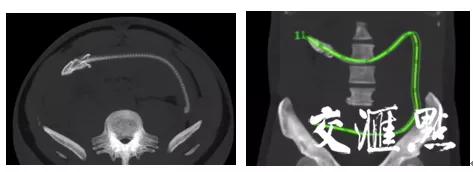

6月8日上午,31岁的男性来到江苏省中西医结合医院肛肠科门诊就诊,自述当天早上9点,一条活黄鳝钻进了他的肛门里!肛肠科副主任中医师葛永盛了解后得知,当时患者已腹胀2小时,查体发现肚子相对较软,直肠空虚,没有粪便也没有发现异物。全腹CT检查示,此时黄鳝的头端在结肠肝区,尾端位于乙状结肠,黄鳝长度大约在40公分。

“针对这种情况,考虑三种治疗方案,一是在内镜下取出,二是由腹腔镜辅助取异物,三是通过剖腹探查。由于病人就诊比较及时,暂时没有腹部体征,而且结肠是一个厌氧环境,黄鳝很有可能已经因缺氧而死亡,所以最终我们选择了在内镜下行结肠异物取出术,手术切口较小,也利于患者的术后恢复。”葛主任说道。初定治疗方案后,葛主任和其医疗团队进行了一系列的术前准备,术中发现黄鳝已经死亡,葛主任利用圈套器抓住黄鳝的尾巴,把黄鳝从患者肚子里拖了出来,整个手术过程只花了十分钟的时间。术后病人无不适症状,病情稳定,生命体征平稳,留急诊观察,行抗感染治疗。